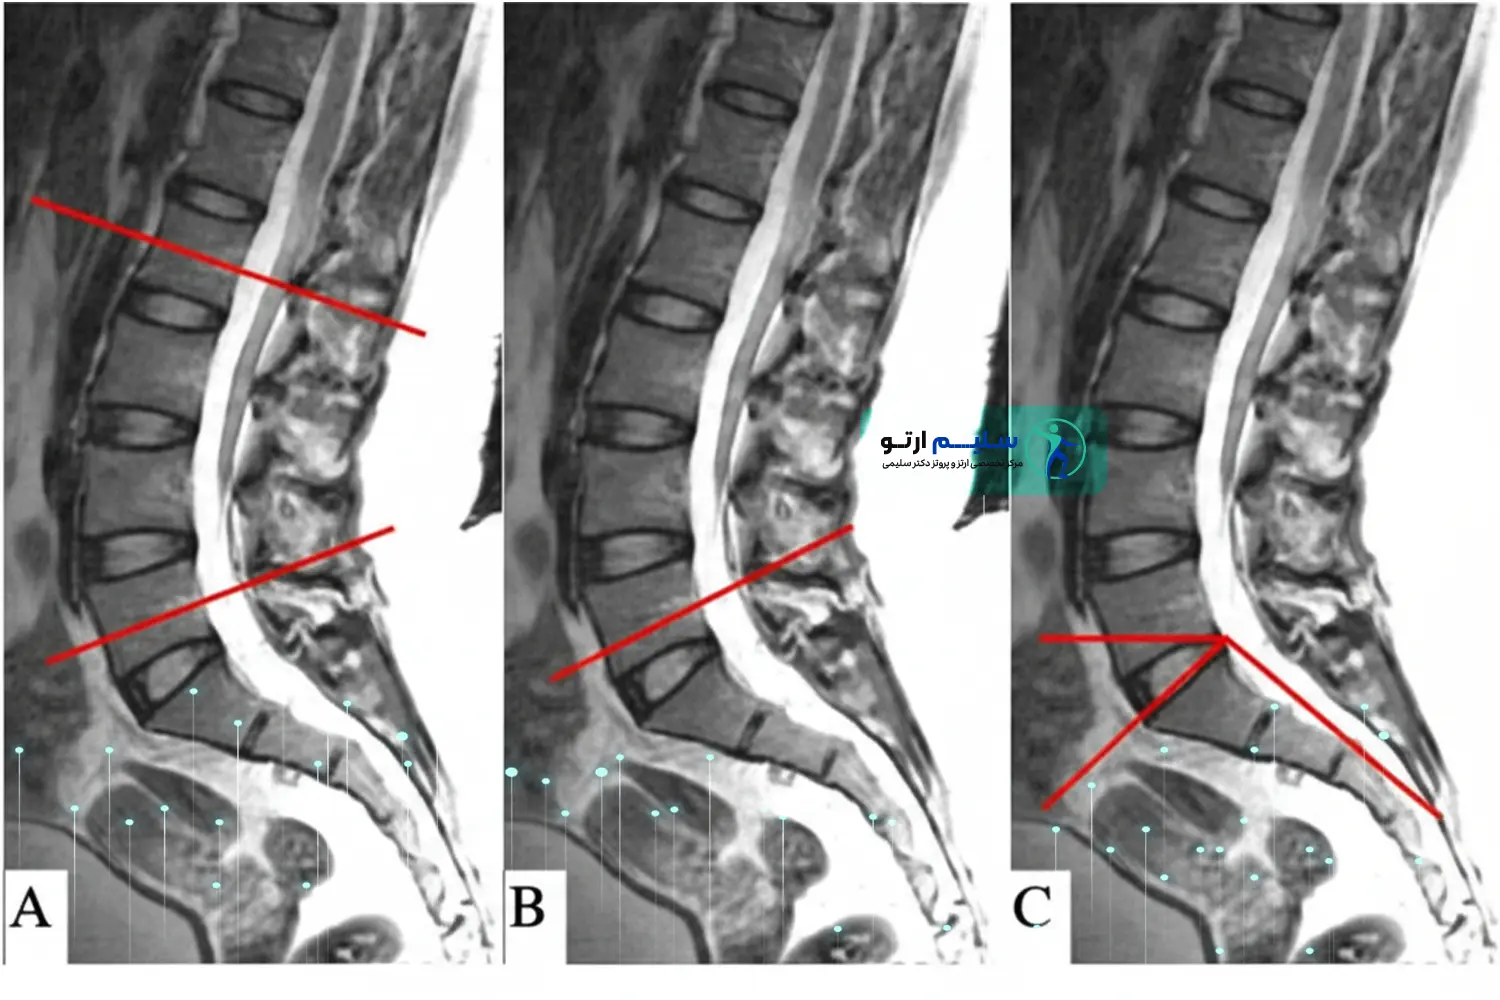

۲.۲ . علل ساختاری و پاتولوژیک (Structural & Disease-Related)

این موارد نیاز به ارزیابی های پیشرفته (مانند MRI و رادیوگرافی) دارند و اغلب مداخلات درمانی پیچیده تری را می طلبند:

| اسپوندیلولیستزیس (Spondylolisthesis) | سر خوردن یک مهره به روی مهره زیرین،که باعث ناپایداری و در نتیجه افزایش لوردوز می شود تا بدن تعادل خود را حفظ کند. | استفاده از ارتزهای کمری سفارشی (LSO Braces) برای تثبیت مهره ها و کاهش حرکت پاتولوژیک. |

- آنالیز تصویربرداری (Imaging Analysis): بررسی عکس های رادیوگرافی (X-Ray) ایستاده برای اندازه گیری دقیق زاویه لوردوز کمری (مثلاً زاویه Cobb). این مهم ترین گام برای تعیین شدت عارضه و نیاز به ارتز است .